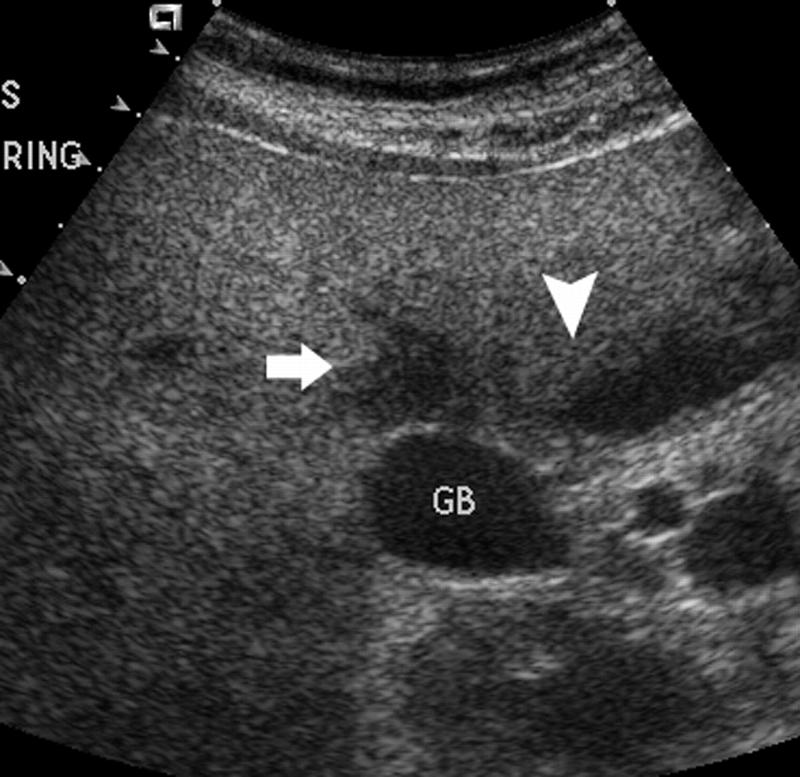

Mirizzi SYndrome

impacted stone in the cystic duct or GB neck

presence of two tubular structures representing the bile duct above the level of the cystic duct

Mirizzi SYndrome

impacted stone in the cystic duct or GB neck

presence of two tubular structures representing the bile duct above the level of the cystic duct